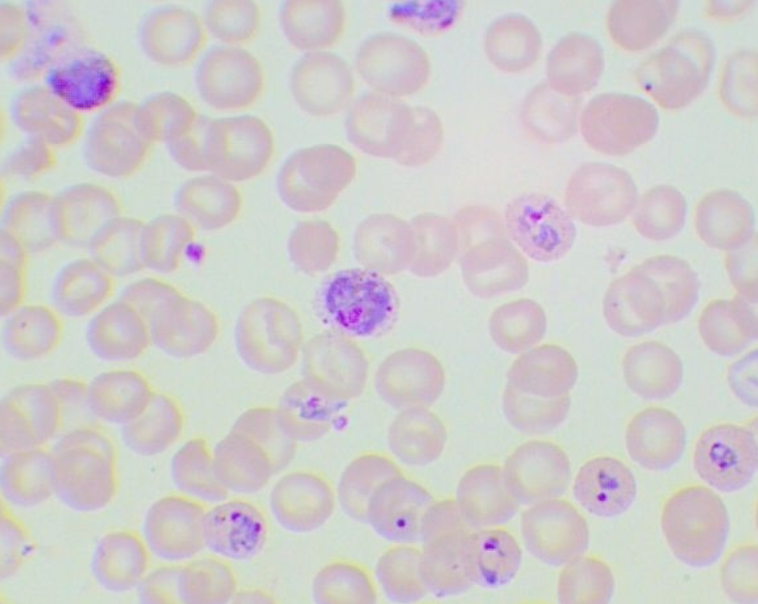

Plasmodium falciparum

Plasmodium falciparum

Plasmodium falciparum